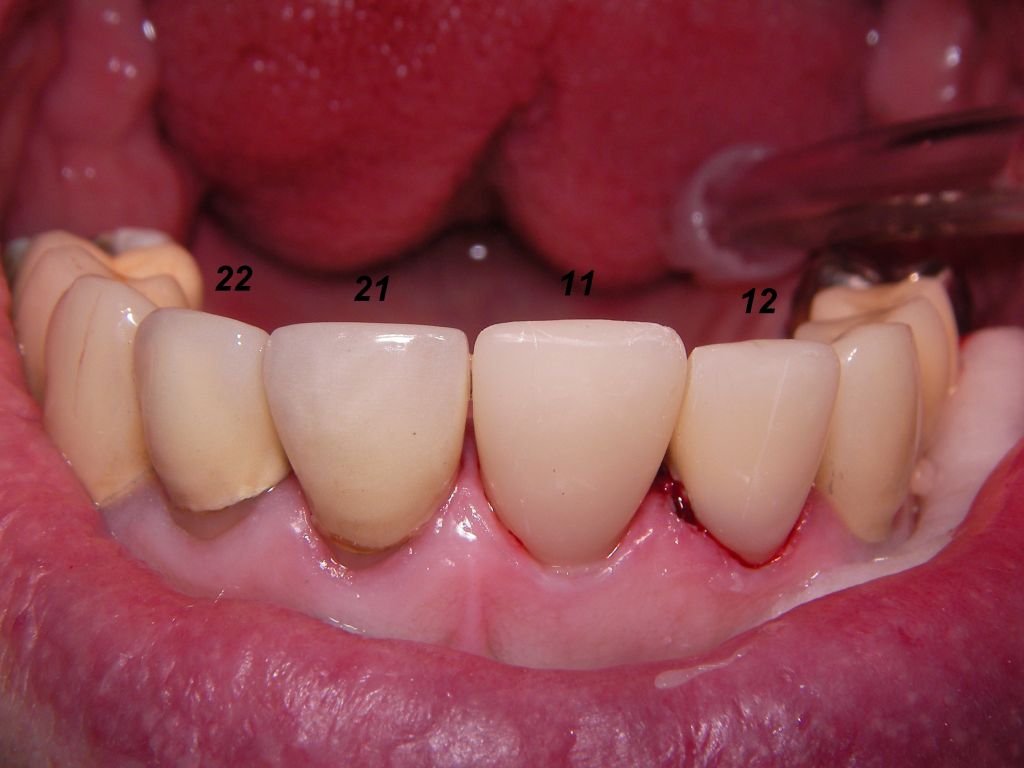

Links das Kontrollfoto nach der Sitzung am 17.2.06. Damit war die Vorbehandlung in diesem Fall abgeschlossen. | |

Links die Kronen aus dem Dentallabor "Heitmeyer Zahntechnik", Osnabrück. Man sieht praktisch keinen Metallrand. Der Patient war zur Farbbestimmung im Dentallabor - so halten wir es praktisch immer. Rechts das Ergebnis bei der 1. Nachkontrolle am 27.3.05. Das Zahnfleisch muß sich noch etwas erholen. |